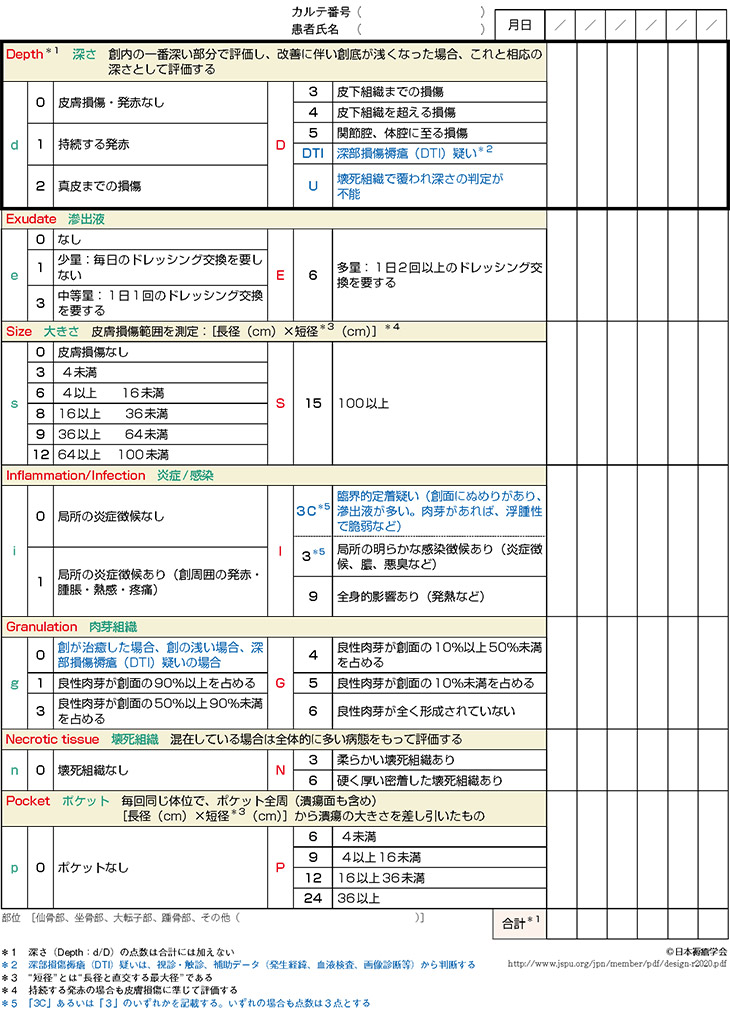

看護師のための褥瘡評価の完全ガイドDESIGN-R評価 - しごとレトリバーガイド。

特集2 DESIGN-R®2020について花王ハイジーンソルーション。

特集2 DESIGN-R®2020について花王ハイジーンソルーション。

特集2 DESIGN-R®2020について花王ハイジーンソルーション。

特集2 DESIGN-R®2020について花王ハイジーンソルーション。

褥瘡の評価 DESIGN-R デザインアール を用いた評価のコツナース専科。

褥瘡評価スケールの種類とDESIGN-R®2020による評価方法 医療従事者対象ネスレ栄養ネット。

褥瘡の評価 DESIGN-R デザインアール を用いた評価のコツナース専科。

看護師のための褥瘡評価の完全ガイドDESIGN-R評価 - しごとレトリバーガイド。